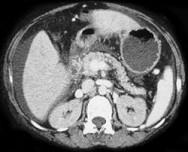

问题 如图,银染色可见系膜区及毛细血管袢有淀粉样物质沉积,刚果红染色呈砖红色阳性,电镜以淀粉样纤维沉积为特点,其病理诊断可考虑为 ( )

选项 A.糖尿病肾病 B.高血压肾损害 C.肾淀粉样变性 D.乙肝相关性肾炎 E.肾小球肾炎

答案 C